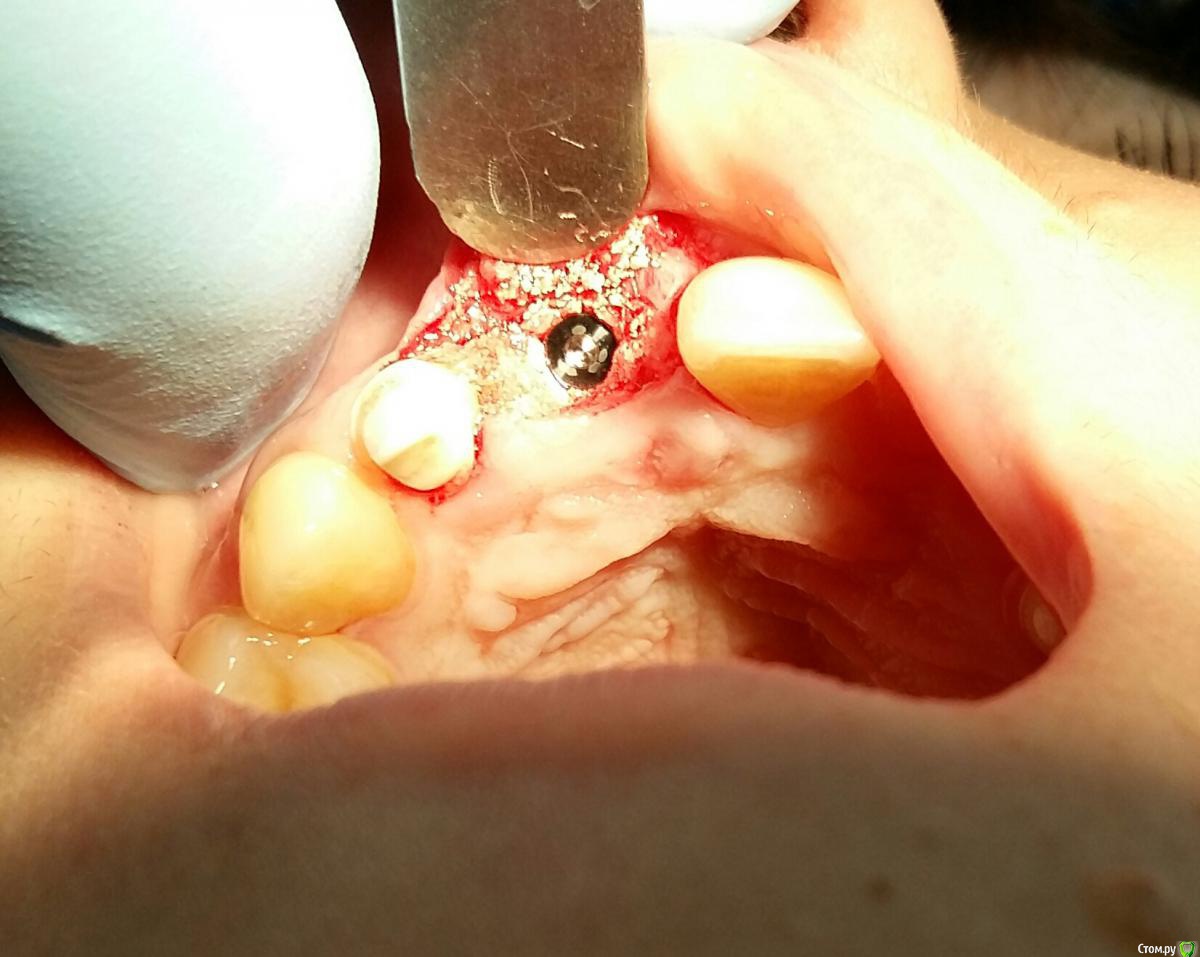

Kostoprav Опубликовано 24 марта, 2015 Автор Поделиться Опубликовано 24 марта, 2015 к сожалению гной таки был - разрез, кюретаж и дренаж.как думаете остеопластику вместе с имплантацией произвести или до? Ссылка на комментарий

Большой Зеленый Опубликовано 24 марта, 2015 Поделиться Опубликовано 24 марта, 2015 Можно вместе с установкой импланта. Ссылка на комментарий

Kostoprav Опубликовано 8 июля, 2015 Автор Поделиться Опубликовано 8 июля, 2015 графт повторно после кюретажа засыпал) Ссылка на комментарий